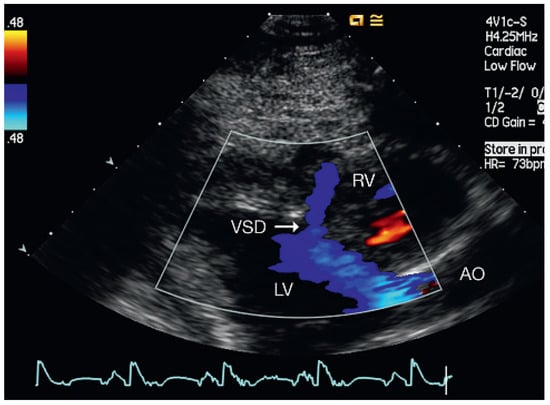

Muscular Ventricular Septal Defect After Mitral and Aortic Valve Replacement